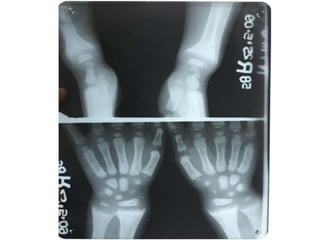

RICKETS

• Demineralization with

coarsening of the

trabecular pattern

• widening of the

epiphysis

• metaphyseal fraying,

cupping and irregularity

at the physeal margin

• Deformity (i.e. bowing)

• flared anterior ribs

RICKETS • Demineralization with coarseningof the trabecular pattern • widening of the epiphysis • metaphyseal fraying, cupping and irregularity at the physeal margin • Deformity (i.e. bowing) • flared anterior ribs